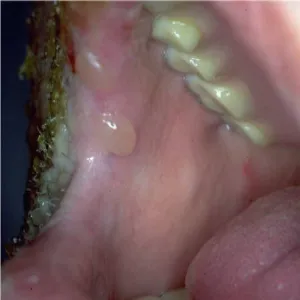

Jama ustna

Jama ustna zdjęcia chorób. Zmiany skórne Jama ustna ZDJĘCIA

Pemfigoid pęcherzowy

Zobacz galerię zdjęć: